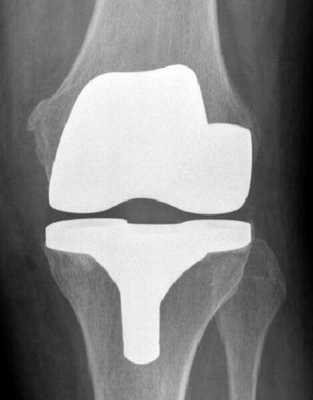

Макет импланта коленного сустава.

Рентген после операции. Протез стоит корректно.